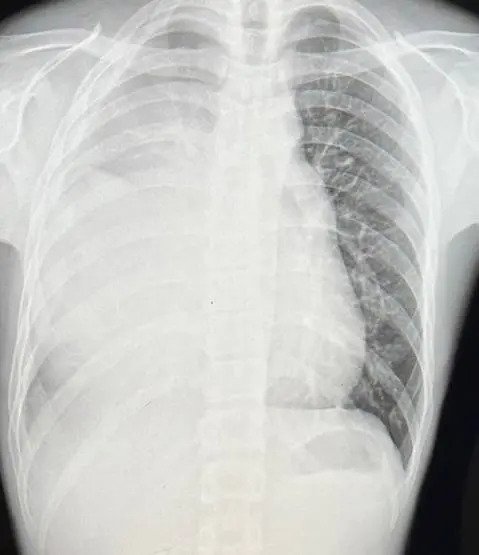

台湾一名男子日前因身体不适看医生,意外发现肺部白了一片,最后被确诊生殖细胞癌,让爱运动、不抽烟的他忍不住崩溃:“我才21岁!”

他日前在网络Dcard平台发文,指自己在7月间因胸痛到医院进行检查,报告显示他的肺部出现一片白色,证实罹癌。

检查后发现,有个15公分大的肿瘤长在纵隔腔处,开始化疗时肿瘤更增长至20公分,经3次化疗后才未持续变大,但也没有缩小。

“我一辈子只剩下一边的肺了,一边已经失去功能了”。